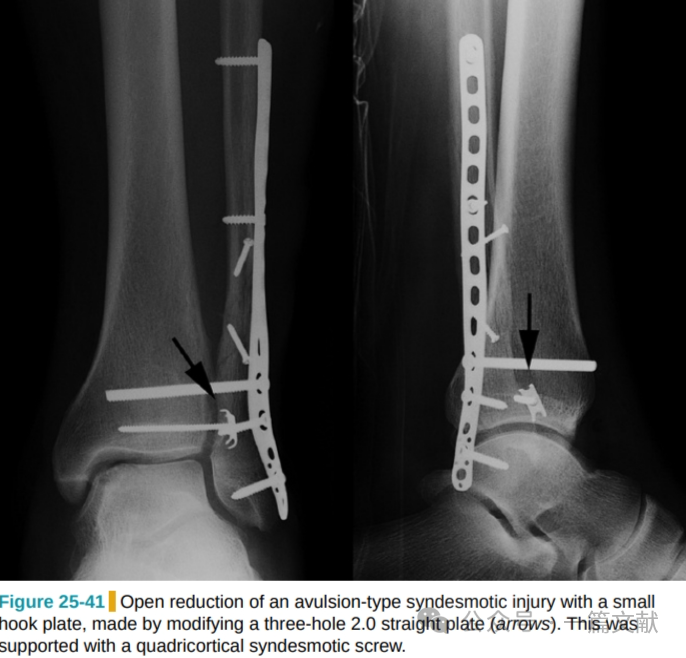

2,合并韧带止点胫骨远端前外侧(chaput)或后外侧骨折块(Volkmann)未解剖复位,造成下胫腓联合的移位。如下图:

此时建议切开复位并内固定,撕脱骨折块较小时可用小的三孔钢板经加工并折弯后固定,如下图: